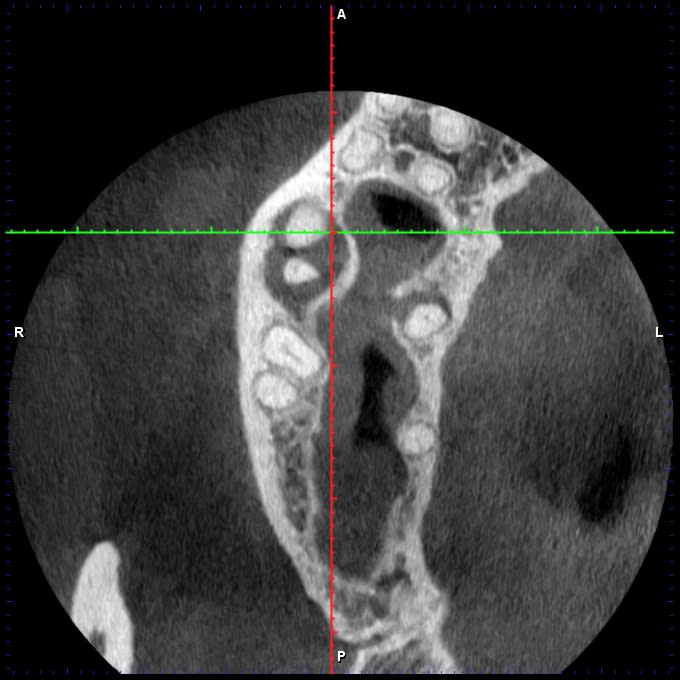

J'ai ce matin un patient qui se présente pour une fracture de 16, asymptomatique.

Test froid négatif, la dent présente une PDP qui radiologiquement ressemble à de la biodentine, cliniquement parait plus blanc.

Je fait une cbct: 4 canaux, lésion infectieuse sur chaque racine et surtout, ce qui ressemble à une résorption interne de la racine palatine.